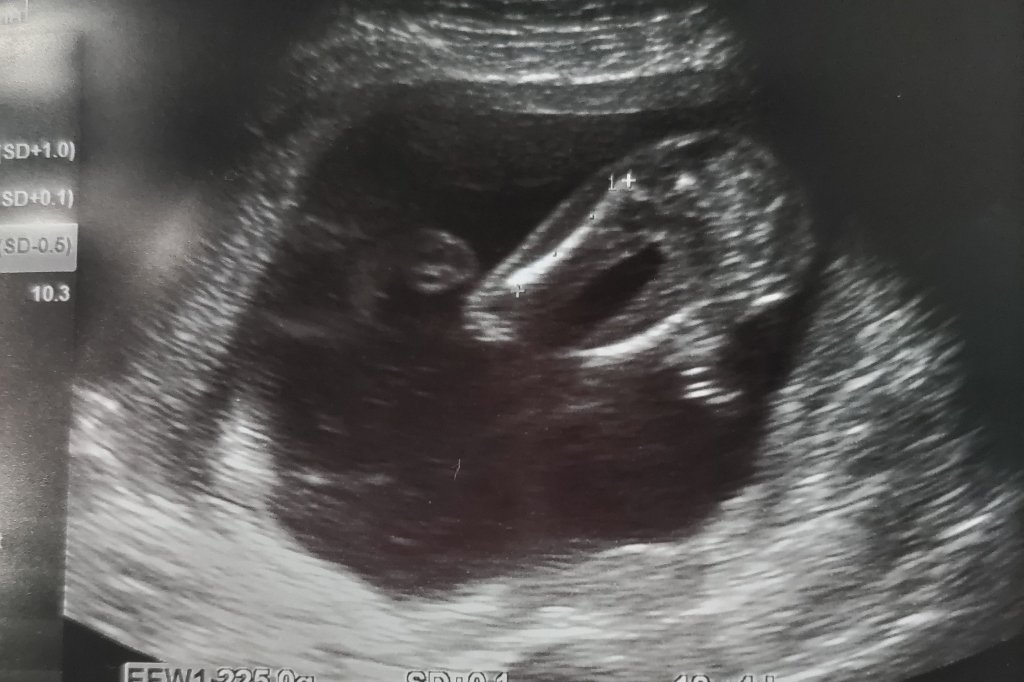

いやはやここまで順調になんとかきました~✨

いまいちはっきりとは性別わからず、今のところ女の子…かな~👧?

らしいです😁

どっちでも嬉しいけど、女の子だといいかな~😊

ちなみに18週あたりから消化器官の形成や耳も形成が始まるらしいですよ😃

1つの細胞から人が出来るのは不思議だよな~🤔